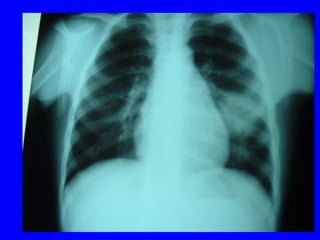

X quang phoåi:  xaùc ñònh , xñònh NN, ñoä naëng

VP thuyø, thaâm nhieãm phoåi, VP moâ keõâ

4.3 Chaån ñoaùn xaùc ñònh:

Laâm saøng: soát+ ho+ thôû nhanh vaø hoaëc co

loõm ngöïc

+ X quang: coù toån thöông phoåi: toån thöông

pheá nang; moâ keõ; toån thöông thuøy phoåi